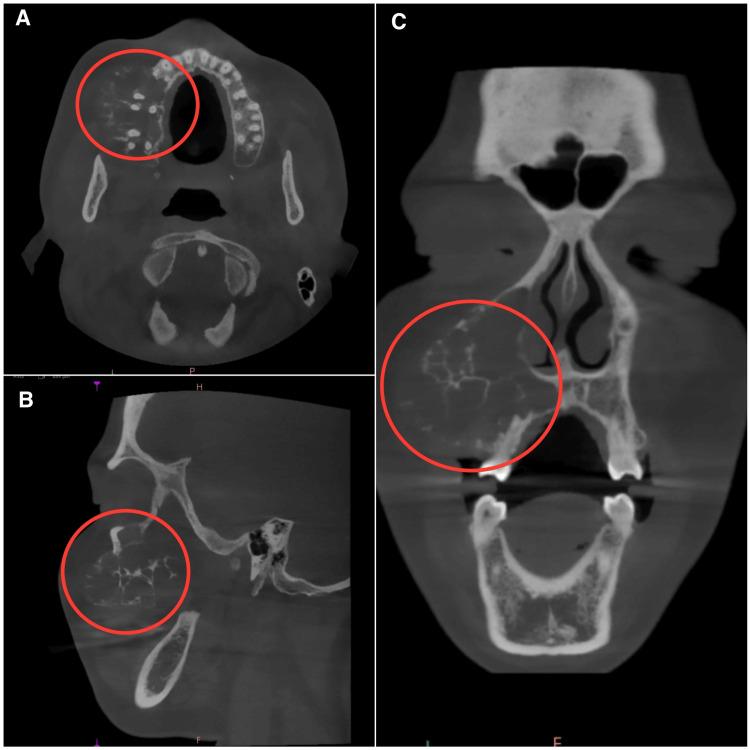

Odontogenic fibromyxoma typically presents as painless swelling in the jaw, and clinically, it grows slowly, becoming benign and asymptomatic. It causes the cortical plates to expand gradually, which leads to mobility and drifting of the teeth. Root resorption is also common. The tumor is locally aggressive in nature. It is also known to have a high recurrence rate. We present the case of a 30-year-old female patient who was diagnosed and treated for odontogenic fibromyxoma of the maxilla conservatively with enucleation. The radiograph showed a multilocular lesion, which can be confused with ameloblastoma, aneurysmal bone cyst, or odontogenic keratocyst. Hence, with proper clinical, radiographic, and histopathological examination, a correct diagnosis can be made and adequate treatment can be planned.

牙源性纤维黏液瘤通常表现为颌骨无痛性肿胀,临床上生长缓慢,呈良性且无症状。它导致皮质骨板逐渐扩张,进而引起牙齿松动和移位。牙根吸收也很常见。该肿瘤本质上具有局部侵袭性,且已知复发率高。我们报告一例30岁女性患者,她被诊断为上颌骨牙源性纤维黏液瘤,并通过摘除术进行了保守治疗。X线片显示为多房性病变,可能与成釉细胞瘤、动脉瘤样骨囊肿或牙源性角化囊肿相混淆。因此,通过适当的临床、影像学和组织病理学检查,可以做出正确诊断并制定适当的治疗方案。